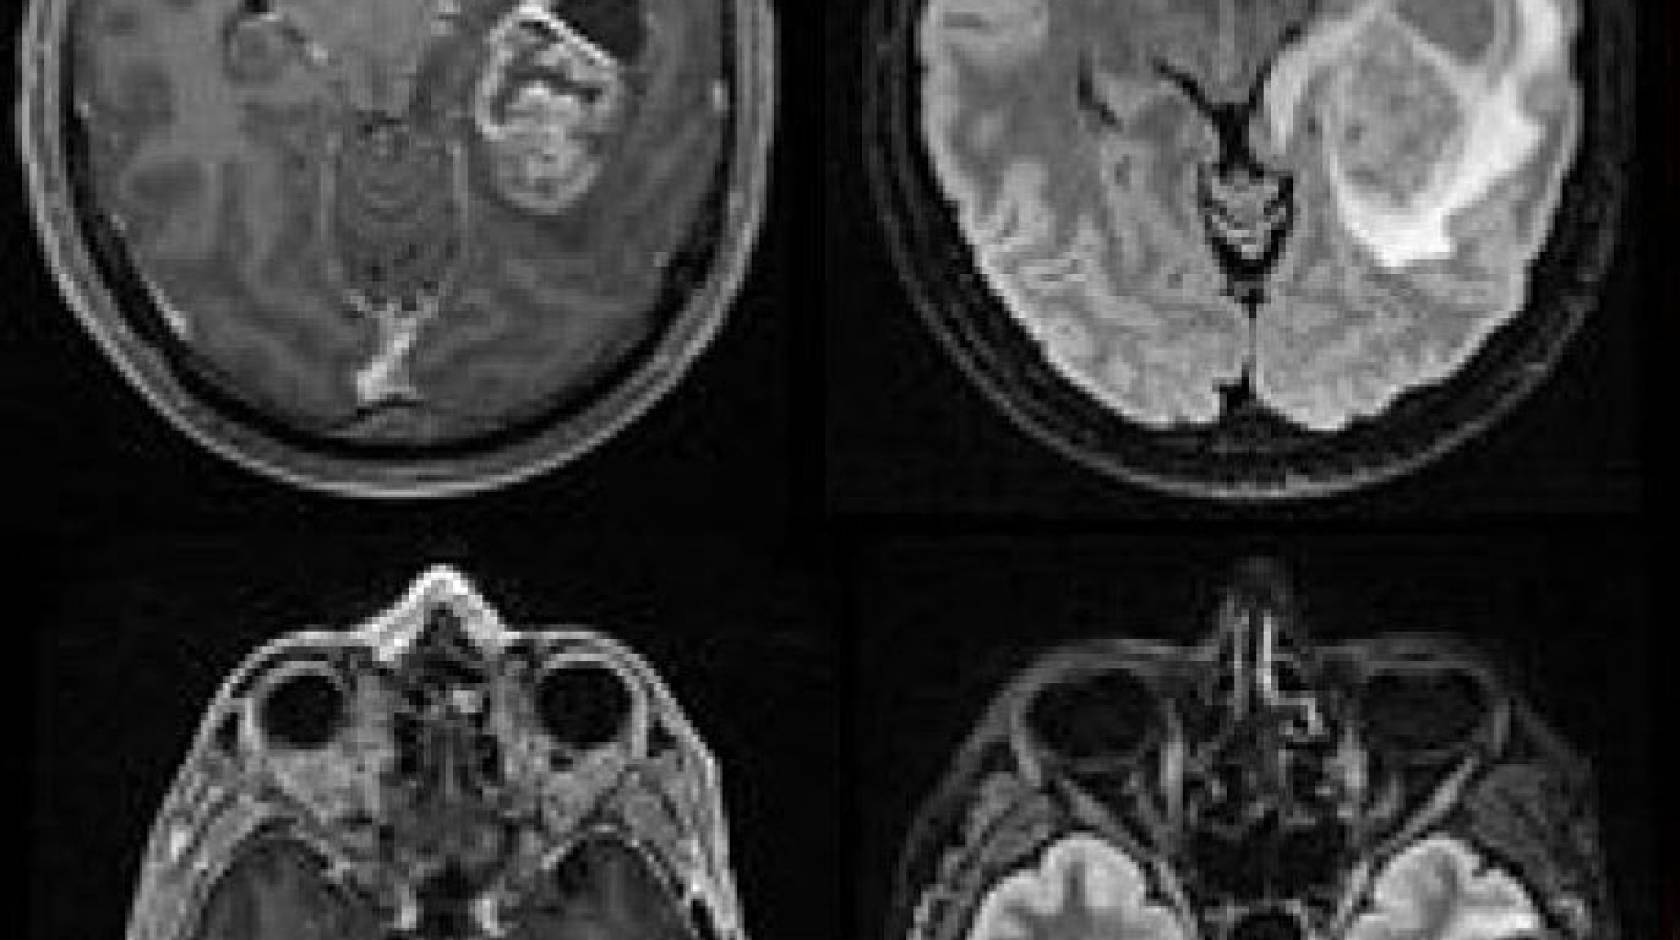

In one paper, research teams led by Wendell Lim, Ph.D., chair and Byers Distinguished Professor of cellular and molecular pharmacology, and Hideho Okada, M.D., Ph.D., the Kathleen M. Plant Distinguished Professor of neurological surgery, tested the system in glioblastoma, the most aggressive form of brain cancer that affects adults and children, and which physicians have yet to successfully treat with immunotherapies due to the complexity of the tumors. The team showed the new system, which uses a two-step process to hunt down cancer cells, could completely clear human patient-derived tumors from the brains of mice without the dangerous side effects or high risk of recurrence currently associated with immunotherapy treatment in solid tumors.

Experiments described in the paper show that this strategy is effective. In mice with human patient-derived glioblastomas, synNotch CAR-Ts wiped out tumors that weren’t cleared by normal T-cells or traditional CAR-Ts, with no signs of dangerous side effects.